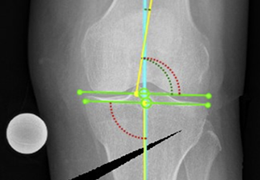

Visualization Tools

Parametric and non-parametric statistical maps may be superimposed both on the original functional scans as well as onto T1-weighted 2D or 3D anatomical reference scans. Time courses of selected regions-of-interest (ROIs) are available both in 2D and 3D representations. Statistical maps may be computed either in the 2D or 3D representation since structural as well as functional 4D data (space x time) are transformed into Talairach space. This allows you to compare activated brain regions across different experiments and across different subjects